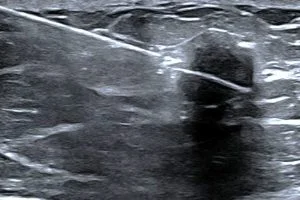

Lorsqu’une lésion suspecte (ACR4 et ACR5) est visible en échographie, on réalise une microbiopsie sous guidage échographique, à l’aide d’un pistolet biopsique automatique.